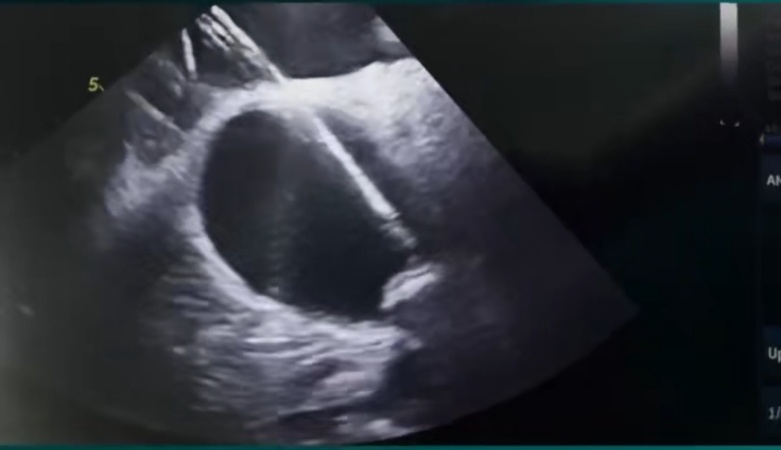

72岁的陈大爷因“反复活动后心累、气促”入院,心电图确诊为:全心增大 三尖瓣反流(重度)二尖瓣反流(中度)左室收缩功能测值减低,少量心包积液,CHA₂DS₂-VASc评分5分(高危),HAS-BLED评分3分(出血高风险)。经多学科评估,患者房颤药物控制效果差,且因既往消化道出血史,无法长期耐受抗凝治疗。为同时解决房颤症状及卒中预防难题,心血管内科团队及DSA介入治疗医学中心决定采用“射频消融+左心耳封堵”一站式手术方案。 术前,介入手术室联合心血管内科、麻醉手术中心、超声医学科、重症医学科等多学科团队,依托Carto三维电解剖标测系统及心腔内超声(ICE)技术,全面重建患者心脏结构,精准定位肺静脉及左心耳。

团队率先为患者实施全麻下房颤射频消融术,随后,经ICE实时引导,将Watchman FLX封堵器精准释放在左心耳开口处,术后造影及超声验证封堵完全无残余分流。

Carto三维系统结合ICE技术,既能提升消融精准度、降低并发症,又可动态评估左心耳形态,确保封堵器完美贴合,尤其适用于左心耳结构复杂或需个体化治疗的患者。